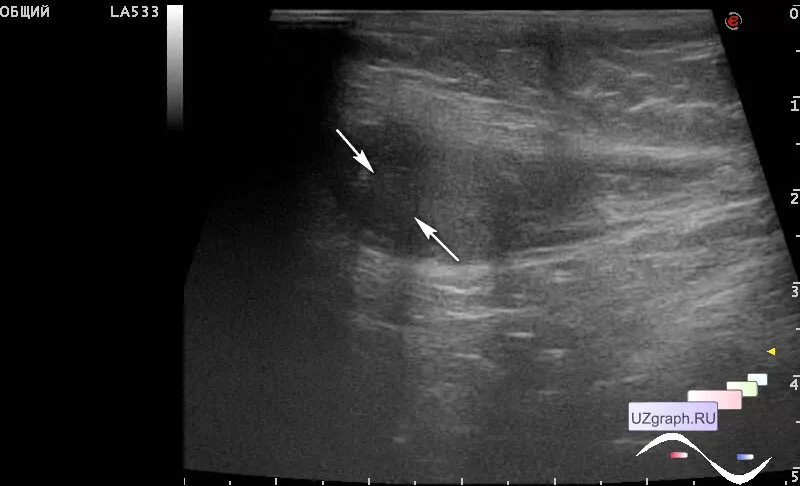

Обеих яичек